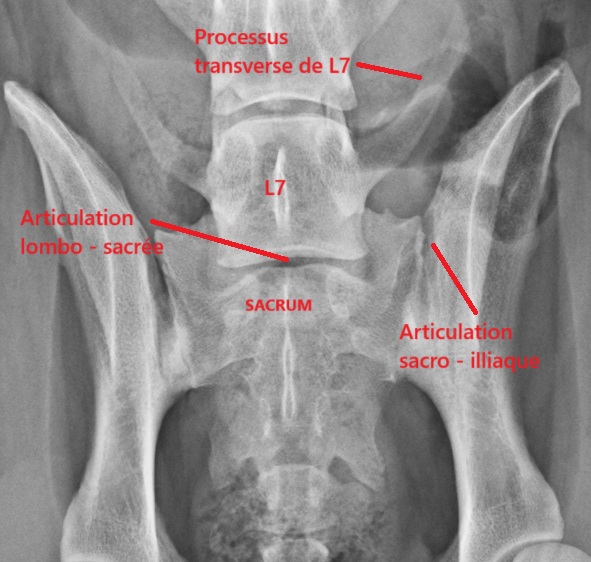

Radiographie du bassin : Anatomie normale

Les vertèbres de transition lombosacrées ou VTL, appelées LTV en anglais (pour lumbosacral transitional vertebrae), ou LÜW en allemand (pour Lumbosakraler Übergangswirbel), sont des anomalies qui touchent la partie terminale de la colonne vertébrale, dans la région des vertèbres lombaires et du sacrum, zone où la colonne vertébrale est reliée au bassin grâce aux articulations sacro-iliaques.